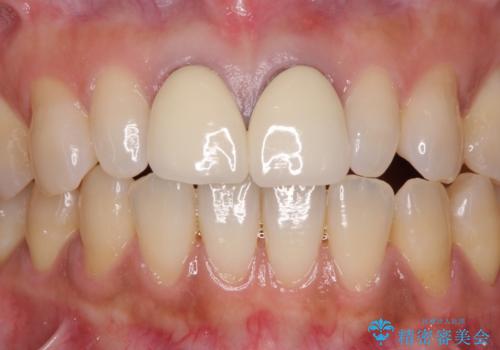

[フルジルコニアクラウン] 老朽化した銀歯を白く

![[フルジルコニアクラウン] 老朽化した銀歯を白くの症例 治療後](https://seimitsushinbi.jp/wp/wp-content/uploads/2020/05/60951366446f010978e24aba6c35e27e-500x350.jpg?v=1588518777)